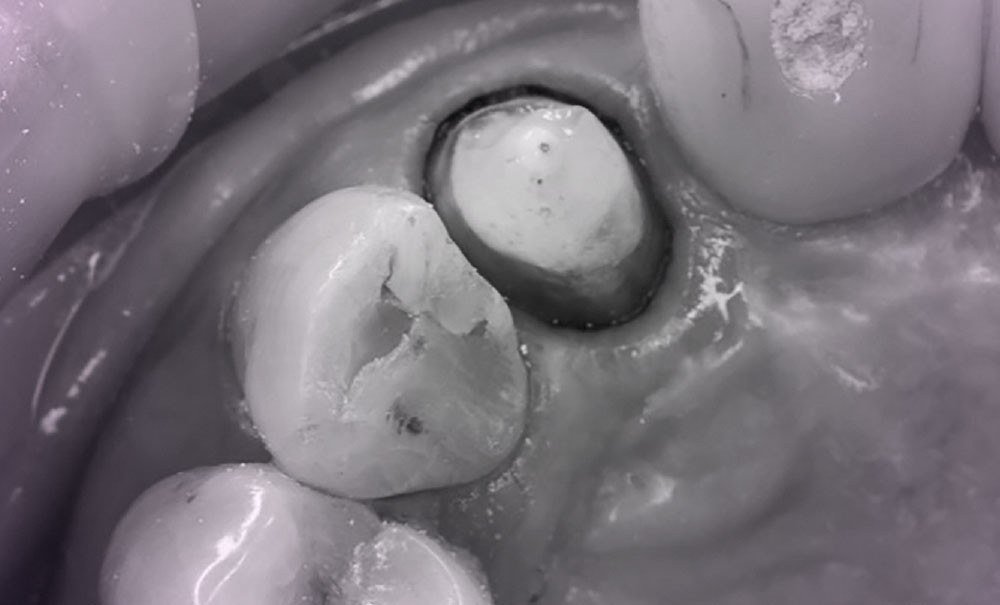

Information dentaire

Depuis quelques années, des nouvelles colles, dites « universelles », ont émergé sur le marché. Elles se présentent comme une avancée des colles auto-adhésives. Leur particularité réside dans leur polyvalence : elles peuvent être utilisées à la fois comme une colle adhésive ou comme une colle auto-adhésive. Ces colles universelles permettent, selon les cas, de s’affranchir de l’utilisation d’un primer prothétique sur la restauration tout en offrant la possibilité d’être combiné ou non avec un adhésif ou primer associé sur la dent. Cette flexibilité est particulièrement utile dans les situations cliniques exigeant une adhésion renforcée. Cet article propose une classification des colles à jour, puis souligne les caractéristiques, les indications et les données récentes sur ces colles universelles, et conclut sur un protocole d’application de ces colles.